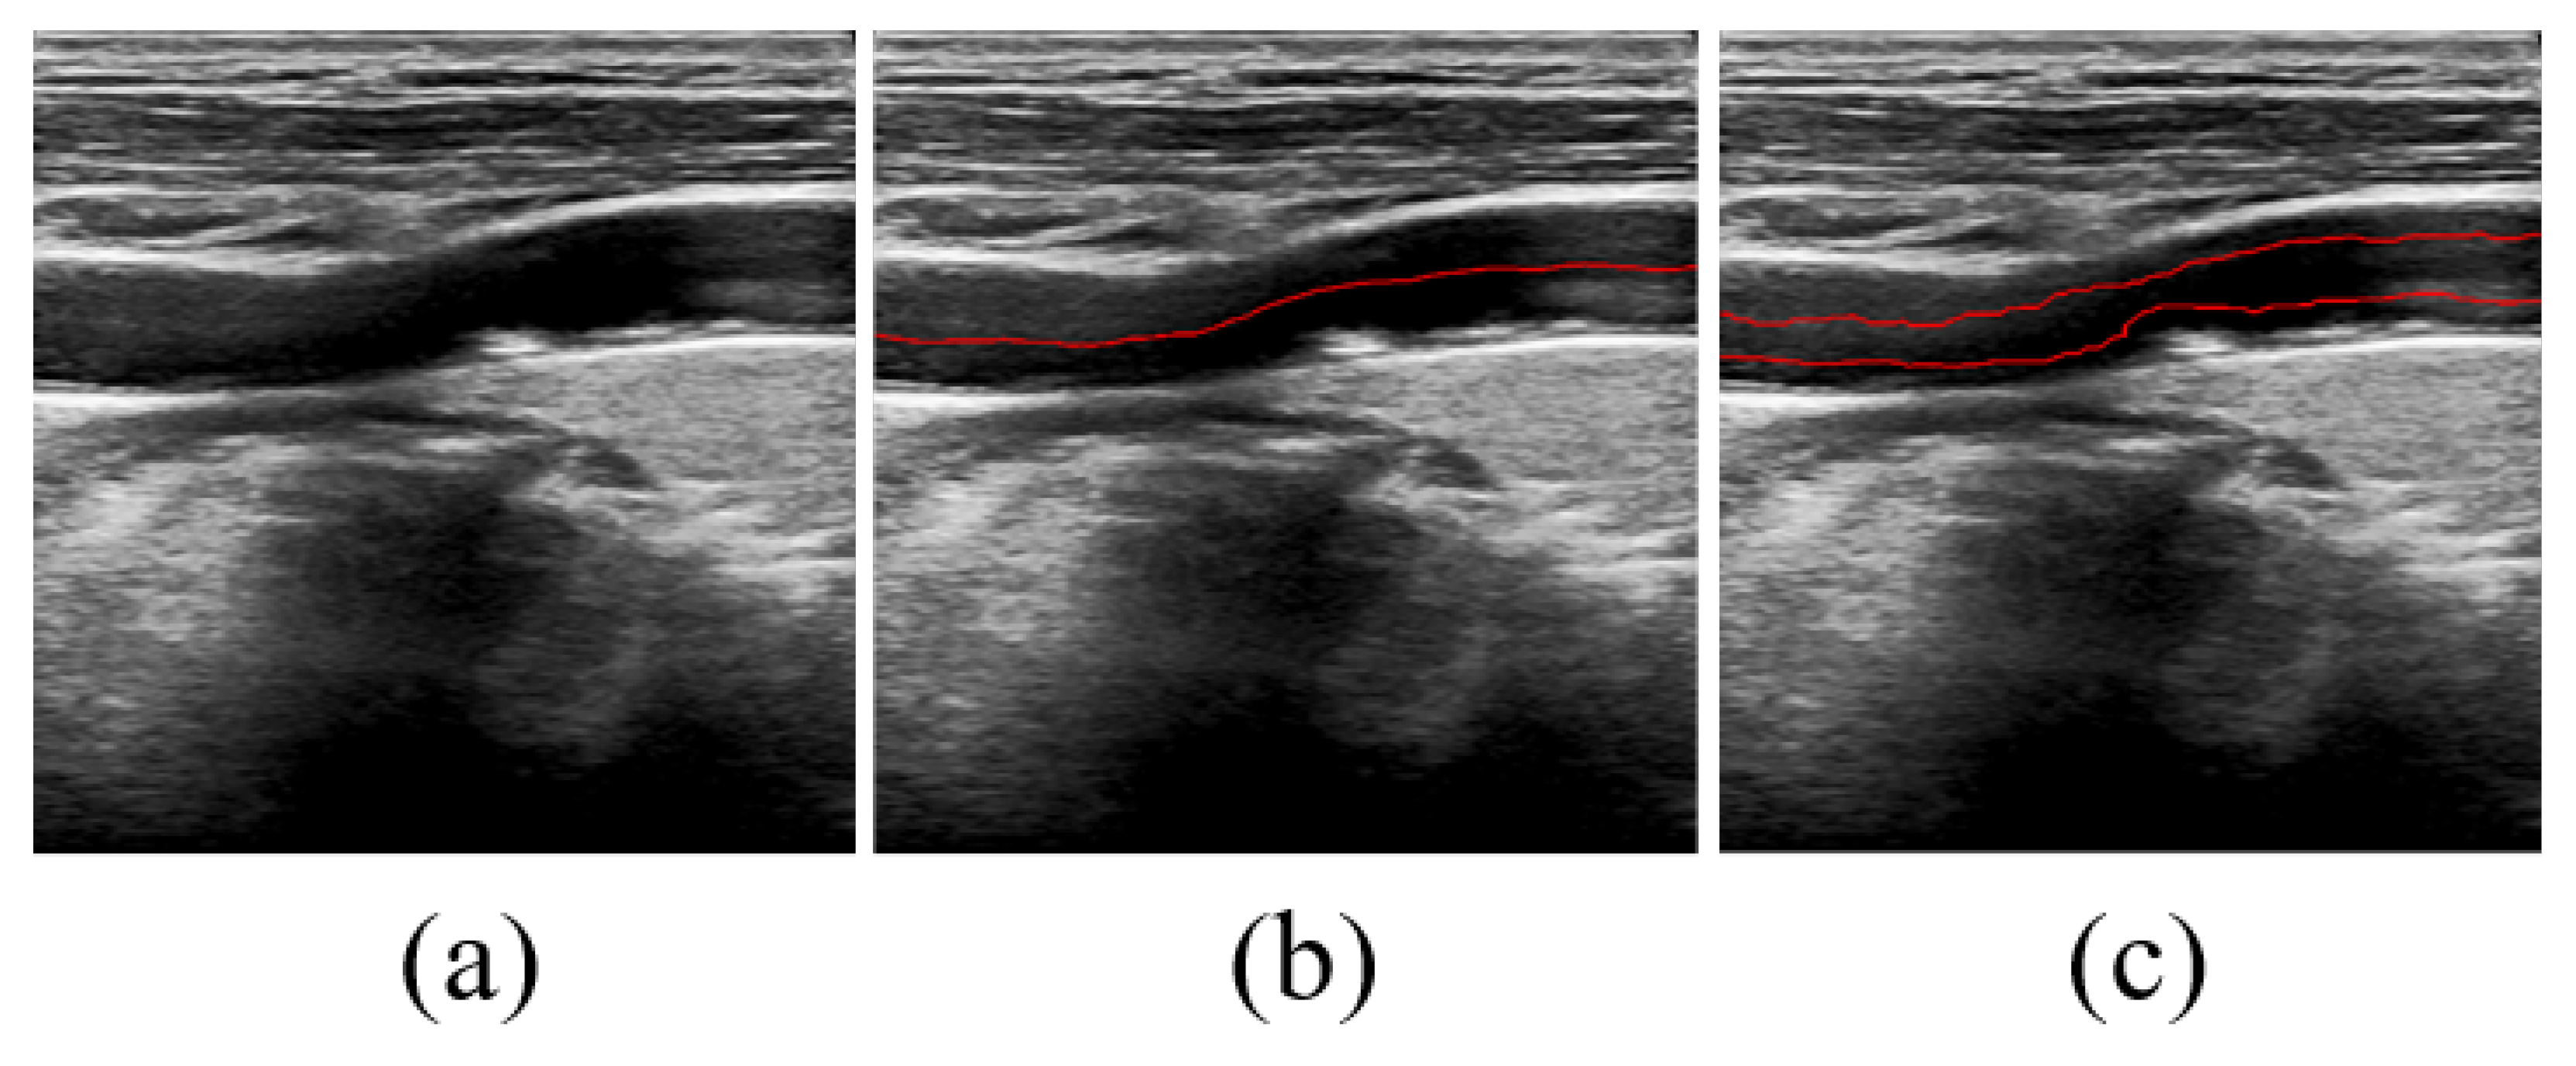

3.4. Experimental Results